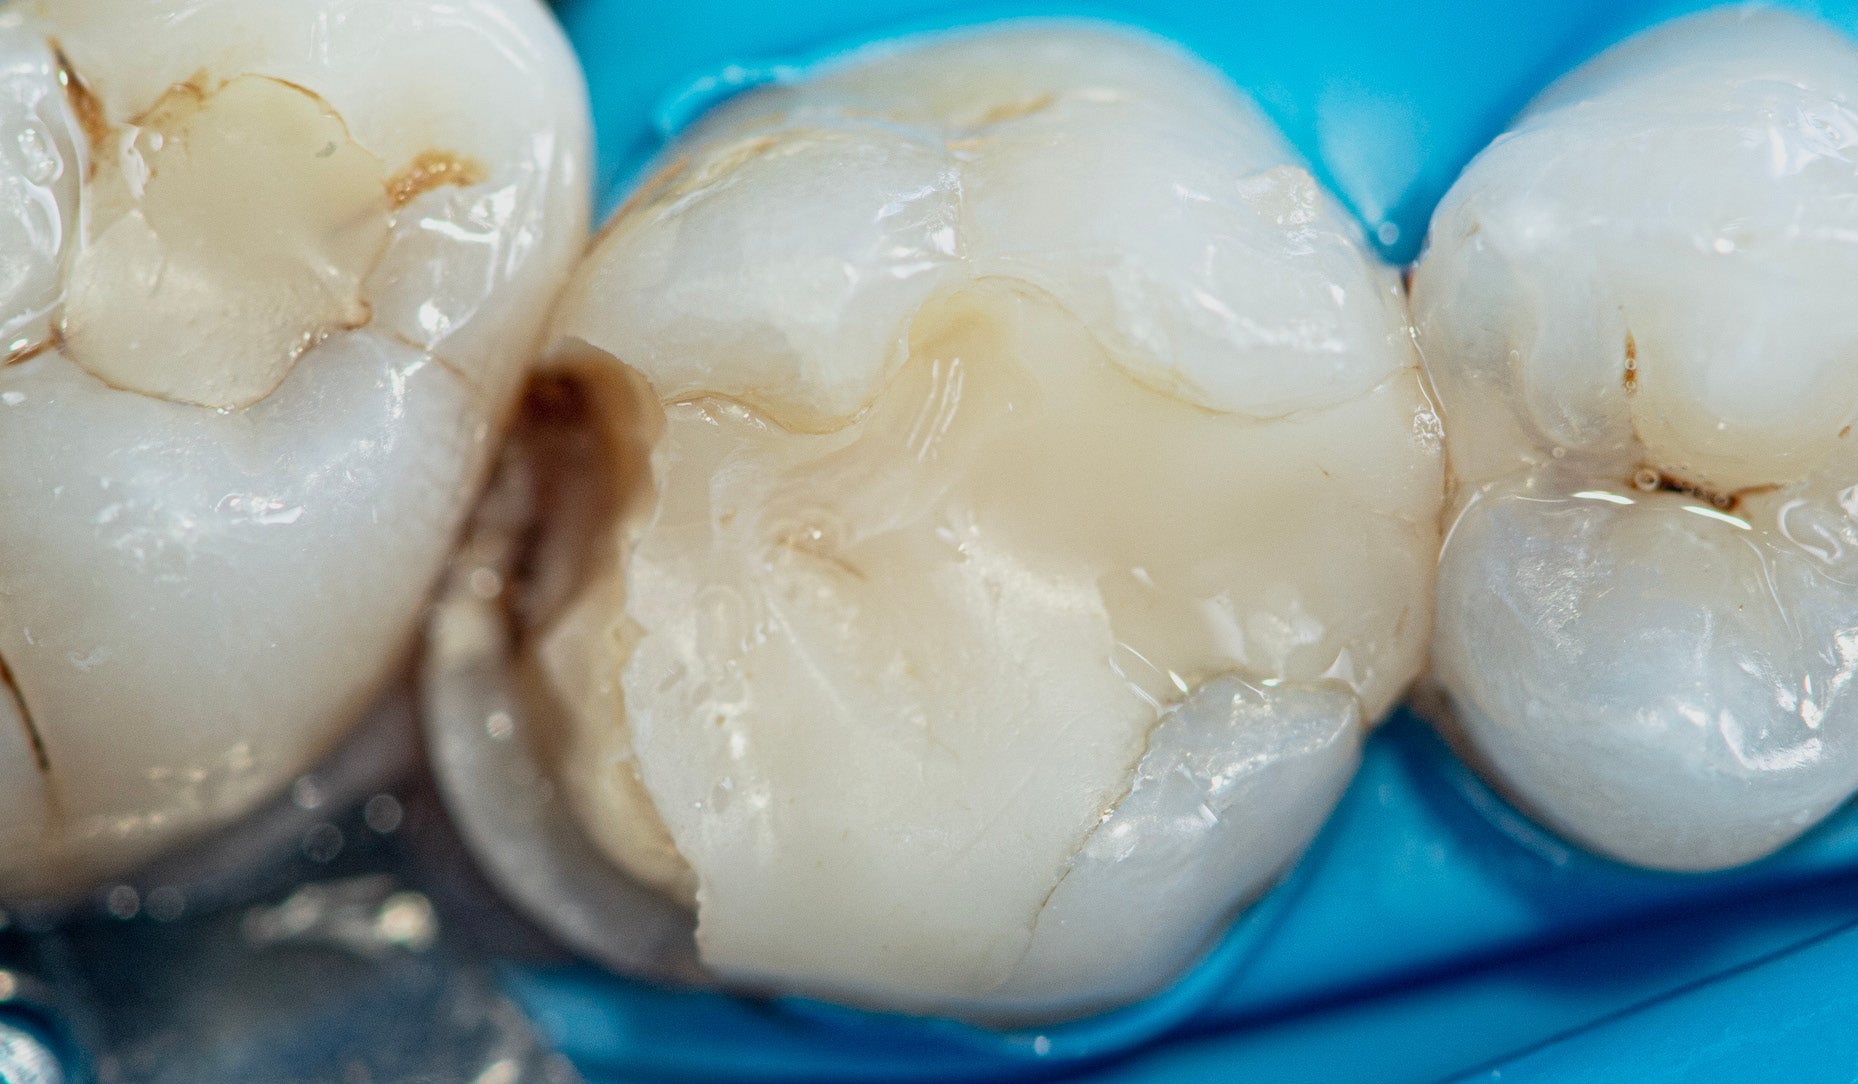

Treatment of a fractured and secondary carious permanent molar tooth Case report by Dr Mediha Isikver Tooth fractures and secondary caries are frequently observed in posterior teeth, often resulting from occlusal stress, restoration failure, or secondary bacterial infiltration. These conditions compromise tooth integrity, function, and aesthetics. With advancements in adhesive dentistry, minimally invasive and durable restorative solutions have become achievable. Material selection plays a critical role in the success of composite restorations, influencing marginal adaptation, wear resistance, and patient satisfaction. This case report describes the step-by-step clinical management of a fractured and secondary carious permanent molar restored using materials from Kuraray Noritake Dental Inc. CASE PRESENTATION A 32-year-old female patient presented to the clinic with sensitivity and discomfort in the upper left posterior region. Clinical examination revealed a distal wall fracture on tooth #26 (maxillary left first molar) with a secondary carious lesion extending subgingivally. Radiographic evaluation confirmed the absence of periapical pathology. Adjacent teeth (#25 and #27) showed early carious activity, but the patient opted for the restoration of tooth #26 only. The tooth was asymptomatic to percussion and showed normal vitality on pulp testing. Fig. 1. Initial clinical view of tooth #26 under rubber dam isolation. TREATMENT PROTOCOL Isolation and caries removal: The tooth was isolated with rubber dam. The existing defective restoration and carious tissue were carefully removed using tungsten carbide burs and a slow-speed handpiece. Surface cleaning: After preparation, KATANA™ Cleaner was applied to remove contaminants and optimize bonding surface quality. Bonding procedure: A single-step, self-etch adhesive, CLEARFIL™ Universal Bond Quick 2, was applied to both enamel and dentin following the protocol recommended by the manufacturer. Restorative phase: The deep and undercut areas were resin coated with CLEARFIL MAJESTY™ ES Flow Universal Low (U shade), ensuring adaptation and stress relief in undercut regions. The remaining cavity was restored incrementally using CLEARFIL MAJESTY™ ES-2 Universal (U shade) paste-type composite, with each 2 mm layer light-cured for 20 seconds. Fig. 2. Clinical view of tooth #26 after removal of the defective restoration and carious tissue. Fig. 3. Application of KATANA™ Cleaner to remove contaminants and optimize bonding surface quality after preparation. Fig. 4. Selective enamel etching performed on tooth #26. Fig. 5. CLEARFIL™ Universal Bond Quick 2 applied to both enamel and dentin following the manufacturer’s recommended protocol. Fig. 6. Resin coating with CLEARFIL MAJESTY™ ES Flow Universal Low (U shade). Fig. 7. Reconstruction of the mesial and distal walls with CLEARFIL MAJESTY™ ES-2 Universal (U shade) composite. Fig. 8. Incremental build-up of cusps and occlusal anatomy using CLEARFIL MAJESTY™ ES-2 Universal composite, refined with a brush for contour adjustment. Fig. 9. Initial finishing of the composite restoration performed with darkcoloured TWIST™ DIA for Composite (medium) rubber points to refine surface texture and anatomy. Fig. 10. Final polishing performed with light-coloured TWIST™ DIA for Composite (fine) rubber points to achieve a highgloss, smooth surface. FINAL SITUATION Fig. 11. Final view of the restoration after occlusal adjustment and polishing. CONCLUSION This case demonstrates that adhesive and restorative systems from Kuraray Noritake Dental Inc. offer a reliable, efficient and effective approach for treating fractured and secondary carious posterior teeth. The integration of self-etch adhesives and high performance composites contributes to durable and aesthetically pleasing restorations. Continuous follow-up is essential to evaluate the long-term clinical behaviour of these materials. Dentist: MEDIHA ISIKVER Dr Mediha Isikver is a graduate of the Ege University Faculty of Dentistry and the co-founder of Klinik M in Istanbul, Turkey. She focuses her professional practice on aesthetic and restorative dentistry, with particular expertise in composite laminate layering, porcelain laminates, and smile design. Believing that every smile tells its own story, she aims to create personalized aesthetic transformations that blend natural harmony with artistic detail. 11 mars 2026 Kuraray Noritake Katana Cleaner Clinical Case Clearfil Majesty Es-2 Universal Restorative Dentistry Pre-Treatment Esthetic Cosmetic Chair Composite Resin Dental Adhesive Clearfil Universal Bond Quick 2 Clearfil Majesty Es-2 Flow Universal TWIST DIA for Composite Visa produkt KATANA Cleaner Visa produkt CLEARFIL MAJESTY ES-2 Universal Visa produkt CLEARFIL Universal Bond Quick 2 Visa produkt CLEARFIL MAJESTY ES Flow Universal Visa produkt Anmäl dig för nyheter Gå med tusentals tandläkare och få gratis råd som kan hjälpa dig och din karriär. Vi kommer inte skräppost eller dela din e-post.